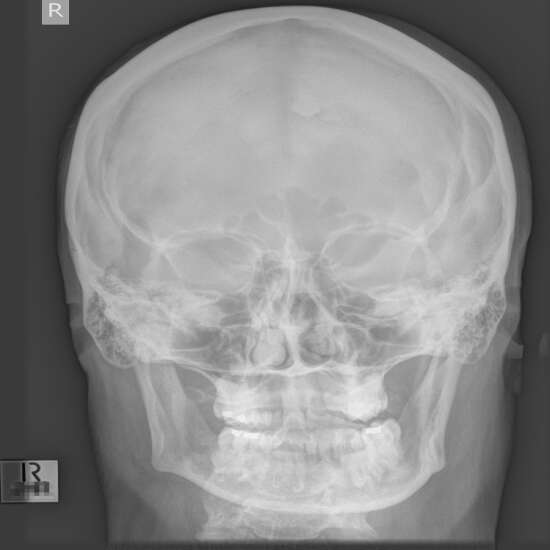

X-Ray Both Mastoid AP

The mastoid is a part of the inner ear that is very important. To work right, the mastoid needs air from the Eustachian tube, which runs from the middle ear to the back of the throat.

If there is an infection in the middle ear, the Eustachian tube might get blocked. This can induce mastoiditis, which is an inflammation of the mastoid bone. This X-ray procedure is one of the few diagnostic procedures used to diagnose and treat mastoiditis.